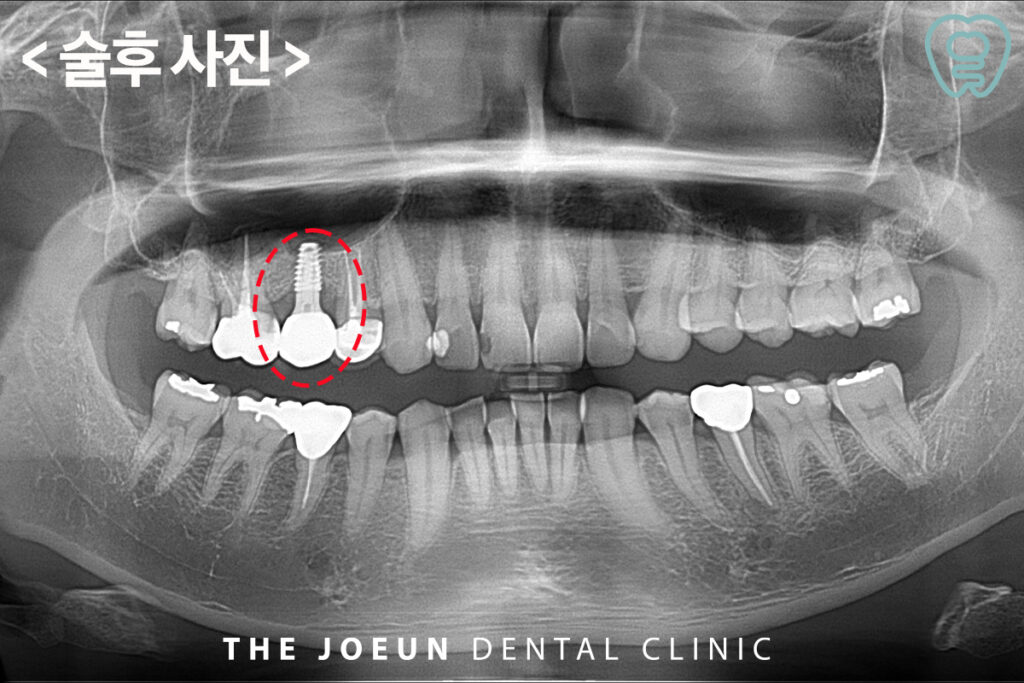

측방 거상법을 통한 뼈이식 후 임플란트 식립을 진행하였습니다.

이와 같이 난이도가 높은 치료의 결정은 잇몸뼈의 상태, 환자의 전신 건강, 시술 부위의 해부학적 조건 등을 종합적으로 고려해 이루어지는데요. 시술 전에는 CT를 통한 정밀 진단이 선행되어야 하며 내부의 해부학적 구조나 점막 두께, 뼈의 높이 등 다양한 요소가 시술의 안정성과 예후에 영향을 미칠 수 있습니다.